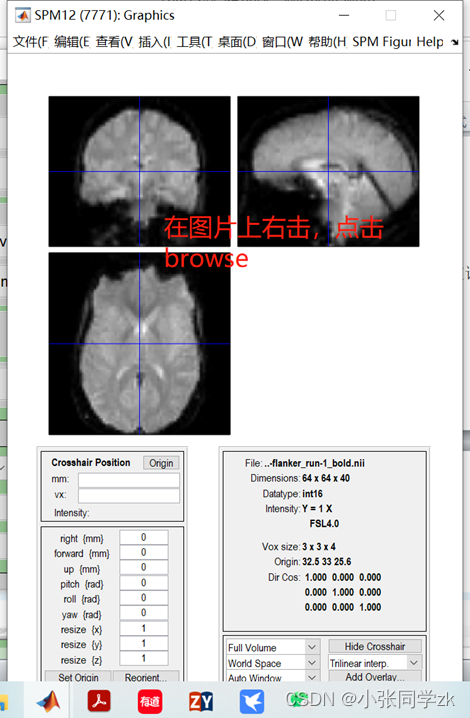

观察功能像:

添加数据:双击session按钮,找到需要添加数据的文件夹路径,选择sub-08_task-flanker_run-1_bold.nii,1 “1”是第一个frame或者volume,我们需要在Filters下面输入1:146(如果不知道多少个volumes,就输入1:1000,这样就会把所有的volumes加载进去),然后点击enter,右键select all,点击done,就得到一个run的所有数据。如下图所示。

为了精确找到文件,在 .* 的左边输入run-1。